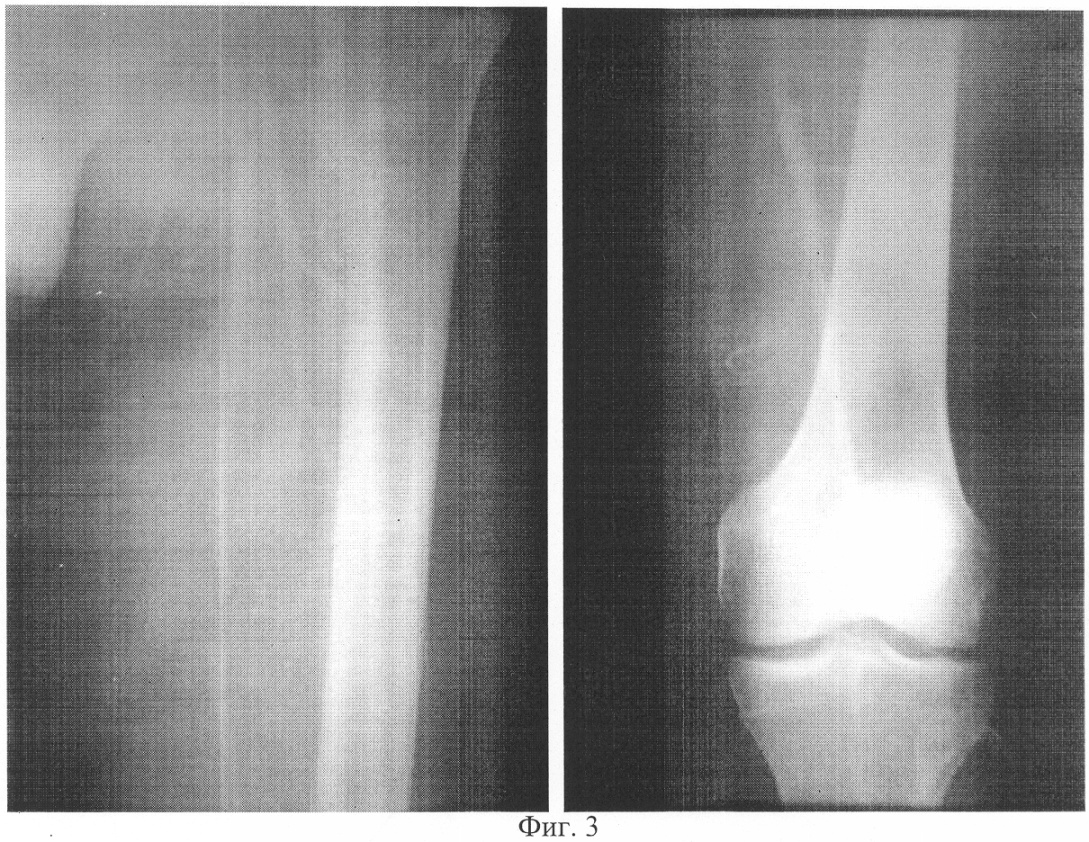

фиг 1. – артериограмма конечности больного Н. до лечения;

фиг.3 – артериограмма конечности больного Н. после лечения;

Больной Н. (фиг.1, 2) поступил в клинику с диагнозом: Сахарный диабет, II тип, субкомпенсация. Синдром диабетической стопы слева. Трофическая язва в области ампутированного II пальца левой стопы. Диабетическая ангиопатия. Перемежающаяся хромота через 150-200 метров. На артериограмме прослеживается локальная (4-5 см) окклюзия поверхностной бедренной артерии в средней трети, многочисленные стенотические поражения магистральных артерий на протяжении голени и стопы.

В послеоперационном периоде в течение 10 дней продолжали курс ранее назначенной медикаментозной терапии. Ранний послеоперационный период гладкий, швы на левом бедре сняты через 10 дней. Признаков тромбоза реконструированного участка артериального русла не отмечается. На артериограмме (фиг.3) определяется проходимая поверхностная бедренная артерия в зоне протезирования.